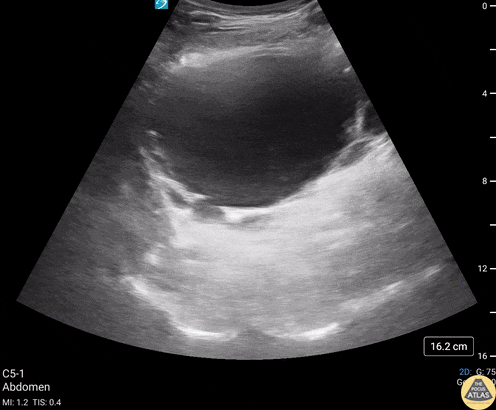

Renal/GU - Bladder Diverticula

82 year old male with history of subarachnoid bleed presented for evaluation after a fall. During a EFAST exam, bladder US revealed multiple, anechoic, cystic-appearing structures consistent with bladder diverticula (confirmed by CT). A bladder diverticulum is a protrusion of the mucosa through the muscular wall of the bladder and can be congenital or acquired. Acquired diverticula are more common, with bladder outlet obstruction being the most common cause. Urology follow up is recommended to confirm the cause and screen for other concerning etiologies or complications including carcinoma, recurrent UTIs and bladder calculi. Contributors: Michael Huber, 4th year Medical Student; Chad Bambrick, MD; Ana Camagay, MD Central Michigan University College of Medicine